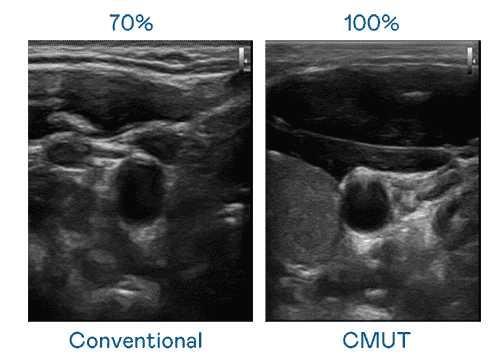

CMUT 技术是一种用电容式微机电元件来产生超音波讯号的技术。。与传统 PZT 压电式技术相比,,,,CMUT 频宽增加 30%,,更宽频的超音波讯号让影像解析度大幅提升,,,,是实现高影像品质医疗超音波扫描、、促进精准医疗发展的关键技术。。

大频宽带来超清晰影像

超音波影像的解析度高低,,首先取决于探头能发出的讯号频宽。。888.BY集团电子游戏 CMUT 可提供高清晰的超音波讯号,,,,提供高频宽、、高灵敏度、、、影像纹理细节更高的超音波影像,,,协助医护人员缩短影像判读时间及利用精准的医疗影像进行诊断。。。。